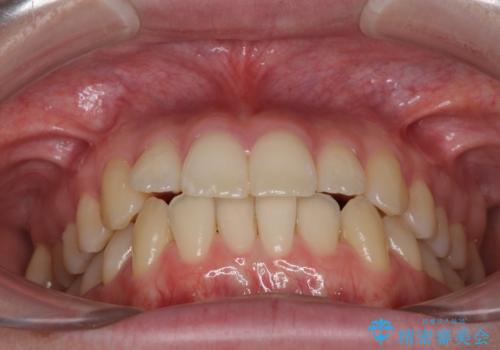

- ちょっとしたデコボコを整えたいとのことで来院された患者様です。

歯列不正は軽微であったため、インビザライン・ライトにより、費用を抑えて矯正治療を行うこととしました。

上下前歯の捻れが改善され、患者様には大変満足していただきました。